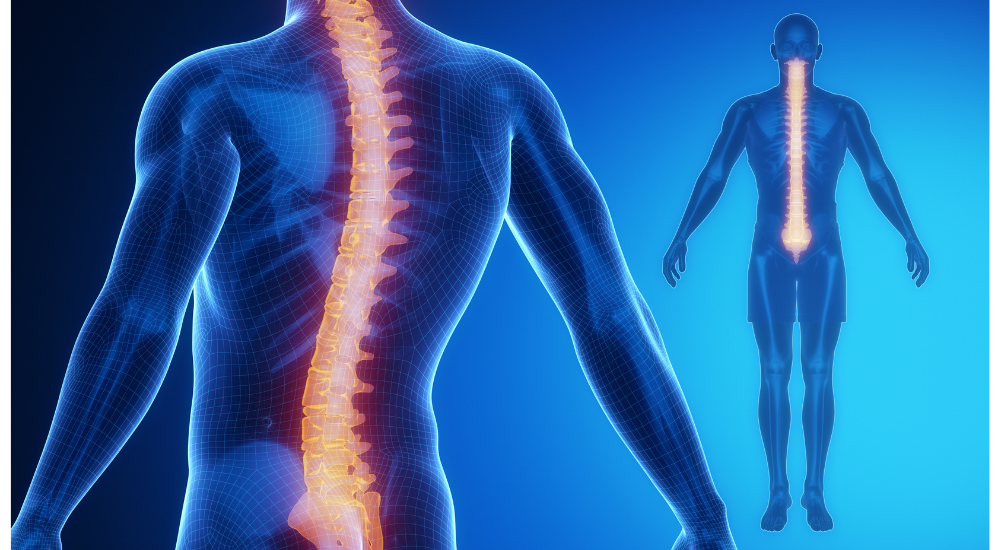

私たちの身体、特に背骨には、重力に対して効率よく身体を支え、衝撃を吸収するための自然なS字カーブがあります。

不良姿勢は、このS字カーブが崩れた状態であり、特定の部位に過剰な負担をかけてしまいます。

- 関節への負担と変性: 不均衡な体重のかかり方が、膝や股関節、背骨などの関節の軟骨のすり減りを早め、変形性関節症のリスクを高めます。